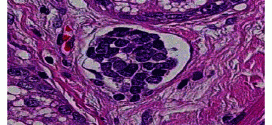

CARCINOMA EPIDERMOIDE DE OÍDO MEDIO

El carcinoma epidermoide de oído medio. Los carcinomas epidermoide de oído medio son raros 1-2/1000000/año. CAE/oído medio: 10/1. Tipo histológico más frecuente Ca epidermoide (70%), seguido del Ca basocelular. Durante los primeros años de vida de una persona, las células normales se dividen más rápidamente para permitir el crecimiento. El cuerpo está compuesto por billones de células vivas. Las células …